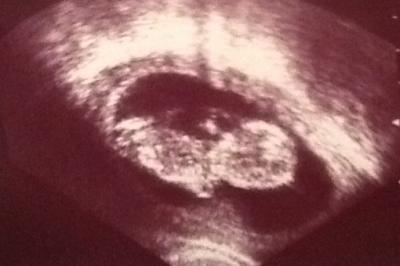

Hallo meine lieben Baldmamis auch ich bin zurück vom Termin und war so unglaublich erstaunt über all die Bewegungen die Erbse da in mir drin veranstaltet hat "Gucken sie mal da winkt es...!" 6cm Groß und sehr agil wie beim letzten mal! Es ist immer wieder eine Freude Anbei ein Bildchen von heute

Bild zu Auch ich hatte heute Termin:) - Forum für März - Mamis